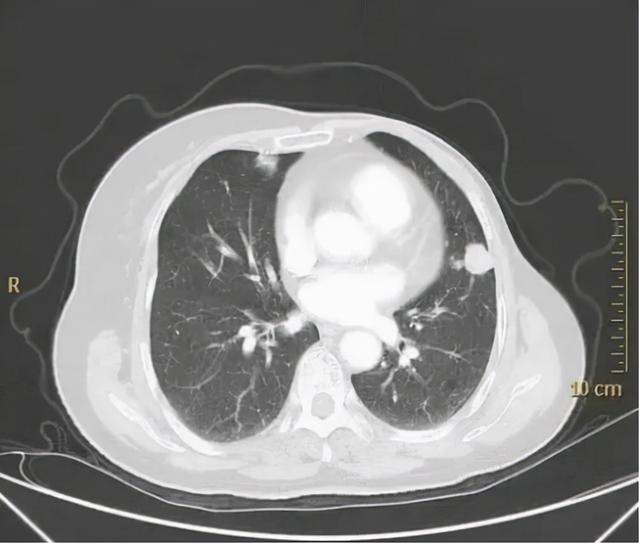

2020年3月,崔女士因反复刺激性干咳到医院就诊。胸部CT复查发现双肺多发圆形结节状阴影,最大的位于左肺下叶,直径约1.5cm,认为双肺多发转移癌。